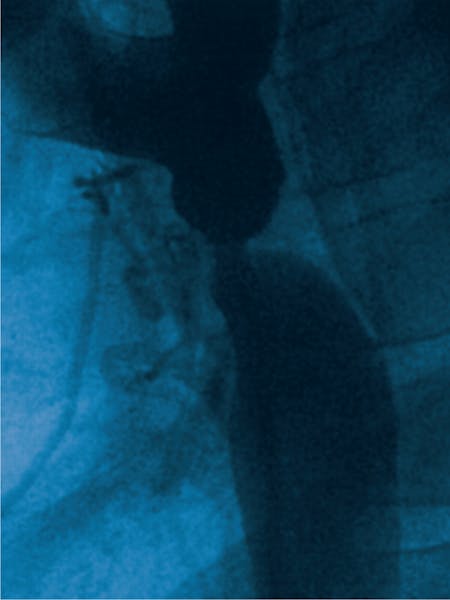

- Aortografia: Este utilizată pentru a obține imagini clare ale aortei și pentru a evalua gradul de îngustare.